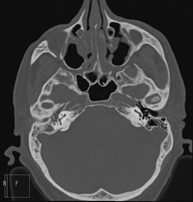

- Paranasal Sinuses CT

Radiological test that provides high definition anatomical images of the paranasal sinuses using CT (Computed Tomography) equipment. Indicated for: headache, mucus, facial infections.